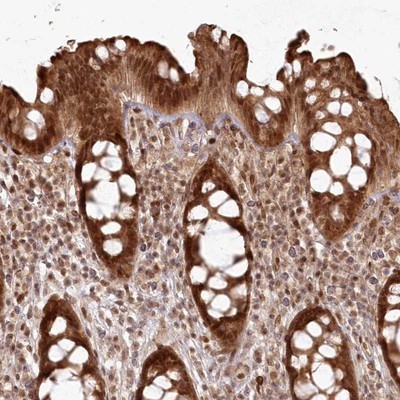

- Main image

- Experimental details

- Immunohistochemistry-Paraffin: FAM179A Antibody [NBP1-93765] - Staining of human colon shows strong nuclear and cytoplasmic positivity in glandular cells.